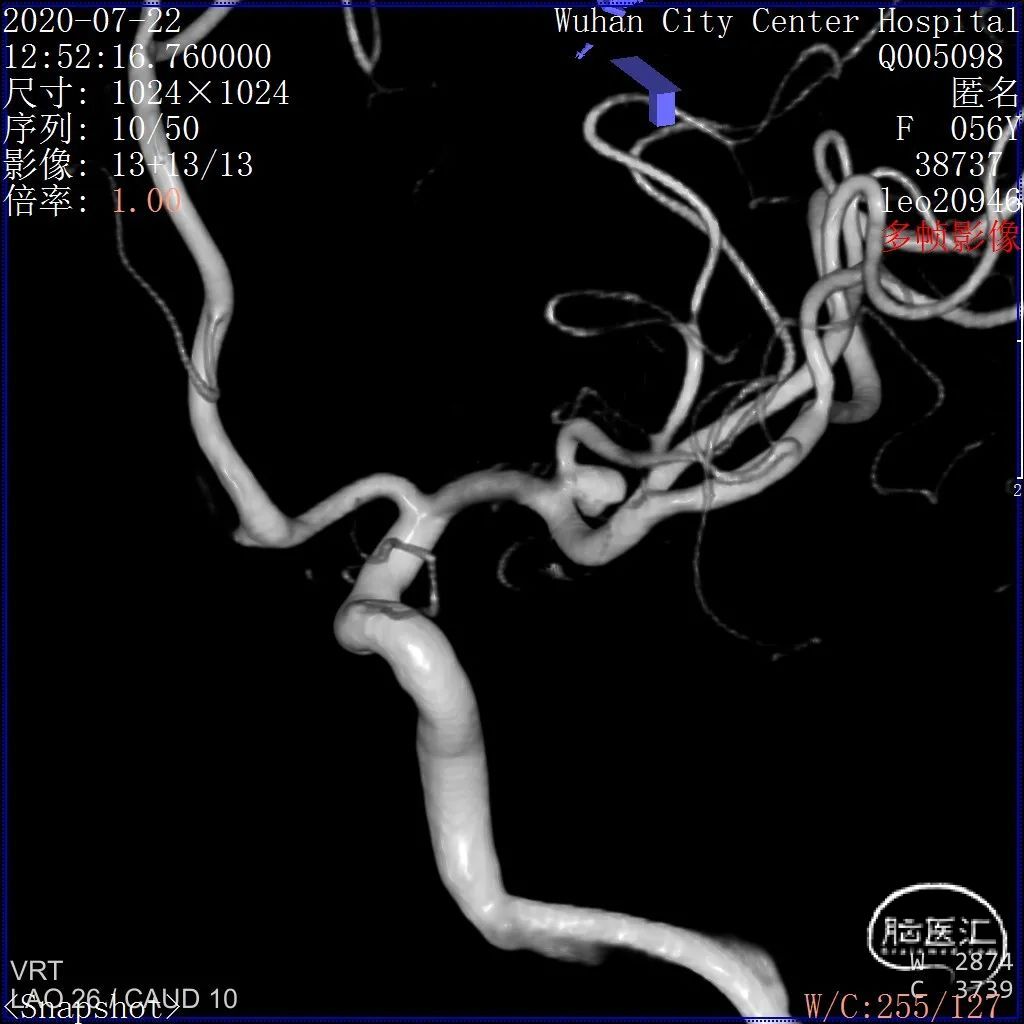

术前影像

DSA 2020-07-22

3D和测量

DSA结果:左侧大脑中动脉分叉部动脉瘤,约3.7*4.1mm,颈宽约2.5mm,形态囊状。